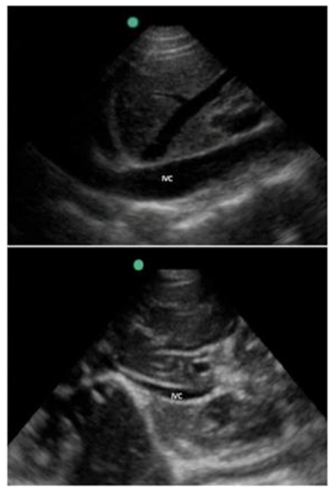

Lactente, 4 meses de vida, 6 kg, é admitido com suspeita de sepse grave. Está hipotenso com PA de 55x35 mmHg, FC de 180 bpm, extremidades frias e tempo de enchimento capilar prolongado. Foi realizado ultrassom dirigido (POCUS) de leito apresentado na imagem a seguir, demonstrando a veia cava inferior na expiração e na inspiração, além do ventrículo esquerdo hiperdinâmico com cavidades pequenas e ausência de derrame pericárdico ou outras anormalidades estruturais significativas.

Com base nos achados do ultrassom e na avaliação clínica, qual é a interpretação fisiopatológica mais provável e qual conduta deve ser realizada inicialmente?